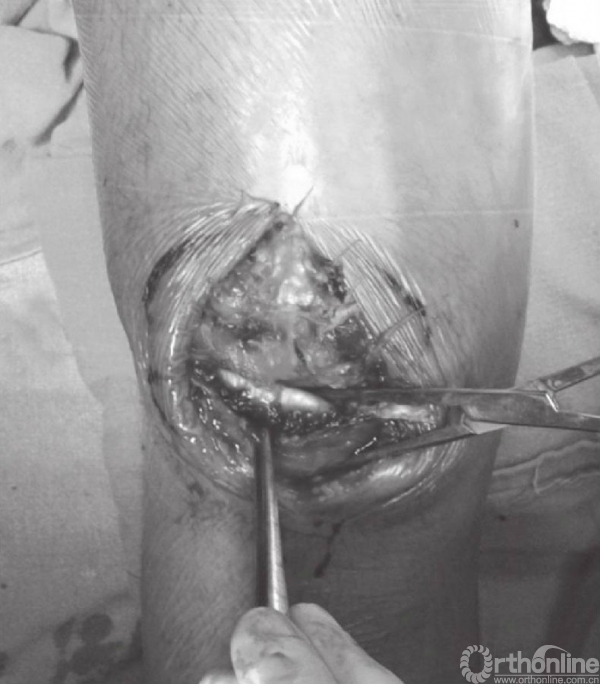

在张力带旋紧固定后,用钢丝剪剪除多余钢丝。突出的部分折弯后贴近髌骨上极放置(图15)。克氏针末端用折弯器折弯后尽量贴近髌骨表面。钢丝末端旋转后经股肌间隙埋入股四头肌腱(图16)。后期缝合肌间隙,可防止克氏针退出。克氏针远端在近髌骨处切断(图17)。用不可吸收线缝合撕裂的支持带(图18)。屈膝90°,以评估内固定的稳定性(图19)。

图17 在近髌骨下极处剪断钢丝